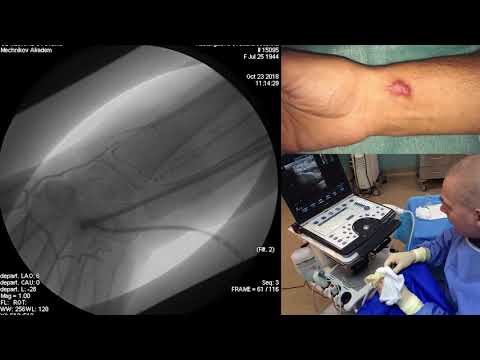

Видеопрезентация дистального лучевого доступа